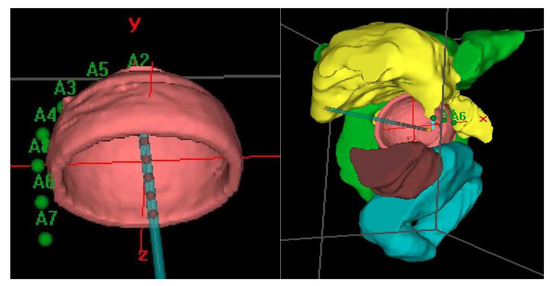

Prior to treatment, a computerized tomography (CT) simulation scan was performed with image acquisition every 1 mm for 3D planning. Special care was taken to confirm close contact of the applicator to the vagina in the CT in order to avoid relapses. Our procedure for clinical target volume (CTV) delineation consists of generating an automatic contour based on the difference in Hounsfield units of the applicator and the patient’s tissues. From this automatic contour, we generate an isotropic 3 mm margin, that is, the expansion volume. Then, a boolean subtraction of the applicator from the expansion volume is made. Finally, manual delineation of the external part of this volume is performed to adapt it to the real thickness of the vagina, which can vary depending on the case and cylinder diameter. For manual delineation, a 2 mm diameter pearl tool is used. The CTV was delineated along the first cylinder and the mean length of the postoperative treated vaginal cuff was 3cm; the rectum, bladder, and sigma were also delineated along 2 cm from the top to 2 cm under the CTV using the Oncentra Brachy planning system (V.4.5.3) (Elekta®,Nucletron BV, Veenendaal, The Netherlands). (Figure 2).

The dose was prescribed at a depth of 5 mm from the applicator surface, and point dose optimization based on distance was used. The active treatment length was 2.5 cm. In the present study, 90% of the isodose surface included the CTV. The voxels corresponding to the vaginal D2cc are always located in a small volume at the top of the vaginal-cuff and any reduction in the dose at this level will consequently reduce the dose at the prescription point. This 2cc volume is described and presented in Figure 3.

Distension of the rectum and air gaps have no impact on the D2cc of vagina considering that the 90% isodose always includes the CTV. The minimum dose of 90% received by 90% of the hottest CTV volume (D90) and the percentage of CTV coverage were calculated as well as the dose to the most exposed 2 cm3 of the rectum, bladder, and vagina. An EQD2(α/β = 3Gy) constraint of 65Gy for rectum and 80Gy for bladder were applied but were never necessary. Dose distribution was not modified to exclude the organs at risk from the dose prescription area. Figure 2 shows the dosimetric study with the area of the vagina most exposed to the dose. After dosimetric evaluation patients underwent treatment with an HDR microSelectron v2 Iridium 192 source and an afterloading source projector (Nucletron® microSelectron V3 digital ELEKTA, Holland, The Netherlands).

Figure 2. Clinical target Volume (CTV) and Organs at risk (OAR) delineation.

Cancers 12 03059 g002